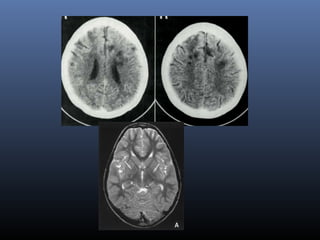

Lacunar infarcts

VRS

Lacunar infarct Virchow Robin

Spaces

Location Ant. To ant. comm

Size 1.5 cm 2 mm

DWI bright dark

FLAIR Peripheral

hyperintense

suppressed